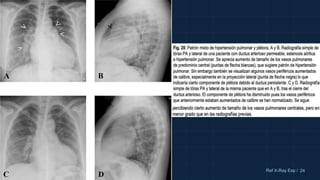

Se identifica un crecimiento de ambos

hilios pulmonares, generalmente de

manera simétrica, a expensas de las

arterias pulmonares derecha e

izquierda y de la arteria pulmonar

principal. Habitualmente acompañado

de disminución de calibre de los vasos

pulmonares periféricos.

PATRÓN DE HIPERTENSIÓN ARTERIAL

PULMONAR

Una medida a recordar para identificar el

crecimiento de las arterias pulmonares en la

radiografía simple PA es el diámetro de la

arteria interlobar: por encima de 16-17 mm se

considera que está dilatada